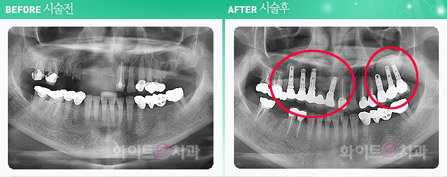

부산 화이트e 치과의 김민경 원장은 임플란트는 물론 치아교정, 치아성형등의 시술을 받기 전 기본적인 사진은 물론이고 CT사진과 진단 모델을 만들어 가상으로 시술을 한 뒤 직접 수술에 들어가기 때문에 그 만큼 실패의 확률을 거의 0%로 만들고 붓기와 통증 등 부작용을 동반할 수 있는 것을 최소화하였다. 또한 수술시 심리적으로 불안해하는 환자들을 위해 수면요법을 병행하므로써 심리적인 안정감까지 고려해서 무엇보다 안전한 시술을 시행한다. 무엇보다 중요한 것은 비용을 줄여 환자를 위한 것이 적어지는 것보다 환자를 위한 필요한 요소를 알고 이것을 최대한 제공하는 것이라고 생각한다.